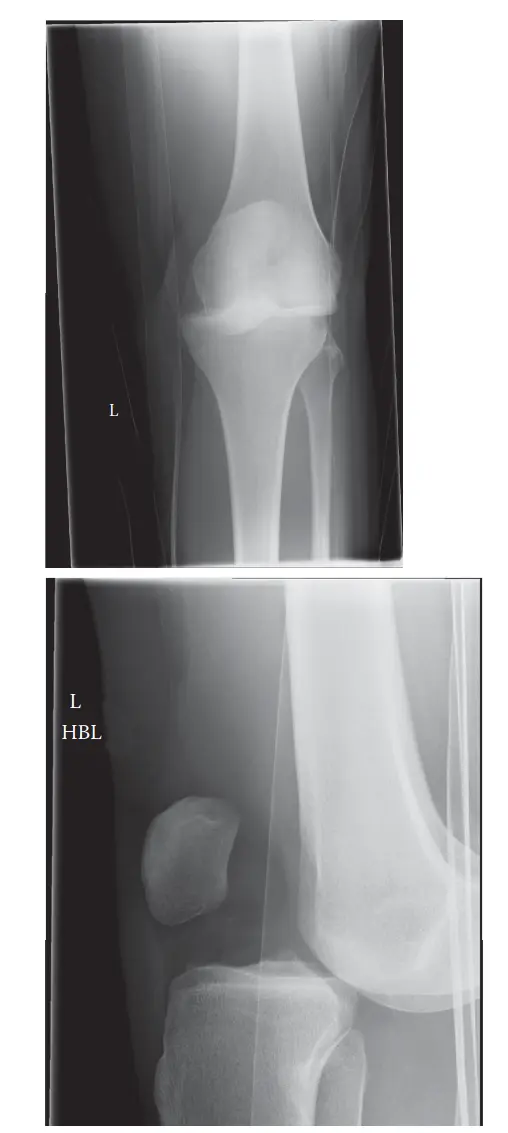

يُعد خلع الركبة من أخطر الإصابات التي قد تصيب مفصل الركبة، فهو يمثل انفصالًا كاملًا بين عظم الفخذ وعظم الساق (الظنبوب). هذه الإصابة لا تقتصر على الأربطة فحسب، بل غالبًا ما تتسبب في أضرار متعددة للأنسجة المحيطة، بما في ذلك الأوعية الدموية والأعصاب، مما يجعلها حالة طارئة تهدد الطرف المصاب. على الرغم من أنها تُعتبر إصابة نادرة نسبيًا، إلا أن تقدير حدوثها قد يكون أقل من الواقع بسبب ميل الركبة للعودة إلى مكانها تلقائيًا قبل وصول المريض إلى المستشفى.

غالبًا ما ترتبط هذه الإصابات بحوادث السيارات، السقوط من ارتفاعات عالية، أو الإصابات الرياضية الشديدة. تتميز عادةً بتشوه واضح في الركبة ومعدلات أعلى من إصابات الأوعية الدموية والأعصاب المصاحبة.

تزداد نسبة حدوثها مؤخرًا، خاصةً لدى مرضى السمنة. يمكن أن تحدث هذه الإصابات نتيجة سقوط بسيط أو التواء في الركبة، وقد لا تظهر بتشوه واضح، مما قد يؤدي إلى تأخر التشخيص أو إهمال عدم الاستقرار الأساسي والإصابات المرتبطة به.

يُستخدم نظام تصنيف شينك على نطاق واسع لتصنيف خلع الركبة بناءً على اتجاه إزاحة عظم الساق (الظنبوب) بالنسبة لعظم الفخذ:

- الخلع الأمامي (KD I): ينزاح عظم الساق إلى الأمام من عظم الفخذ. هو الأكثر شيوعًا، وغالبًا ما يحدث بسبب فرط بسط الركبة.

- الخلع الخلفي (KD II): ينزاح عظم الساق إلى الخلف من عظم الفخذ. غالبًا ما يحدث بسبب ضربة مباشرة على الجزء العلوي من عظم الساق مع ثني الركبة.

- الخلع الإنسي/الوحشي (KD III): ينزاح عظم الساق إلى الداخل (إنسي) أو الخارج (وحشي) من عظم الفخذ. يحدث نتيجة إجهاد تقوس الركبة للداخل (فحج) أو للخارج (روحاء).

- الخلع الدوراني (KD IV): مزيج من الإزاحات.

- الخلع غير القابل للرد (KD V): يحدث عندما ينحشر لقمة عظم الفخذ عبر محفظة المفصل أو تتداخل الأنسجة الرخوة، مما يمنع رد الخلع يدويًا.

متى تحتاج خلع الركبة للتدخل الطبي الجراحي

تُعد إدارة خلع الركبة جراحية في الغالب، نظرًا للتمزق الشديد في الأنسجة الرخوة واحتمال كبير لعدم الاستقرار طويل الأمد والعجز الوظيفي. يُعد التقييم الأولي والرد وتثبيت الأوعية الدموية والأعصاب من الأولويات الحادة. عادة ما يتم اتخاذ قرار العلاج الجراحي النهائي مقابل العلاج غير الجراحي بعد معالجة المشكلات الحادة التي تهدد الطرف وإكمال تقييم شامل للإصابة (بما في ذلك التصوير بالرنين المغناطيسي).